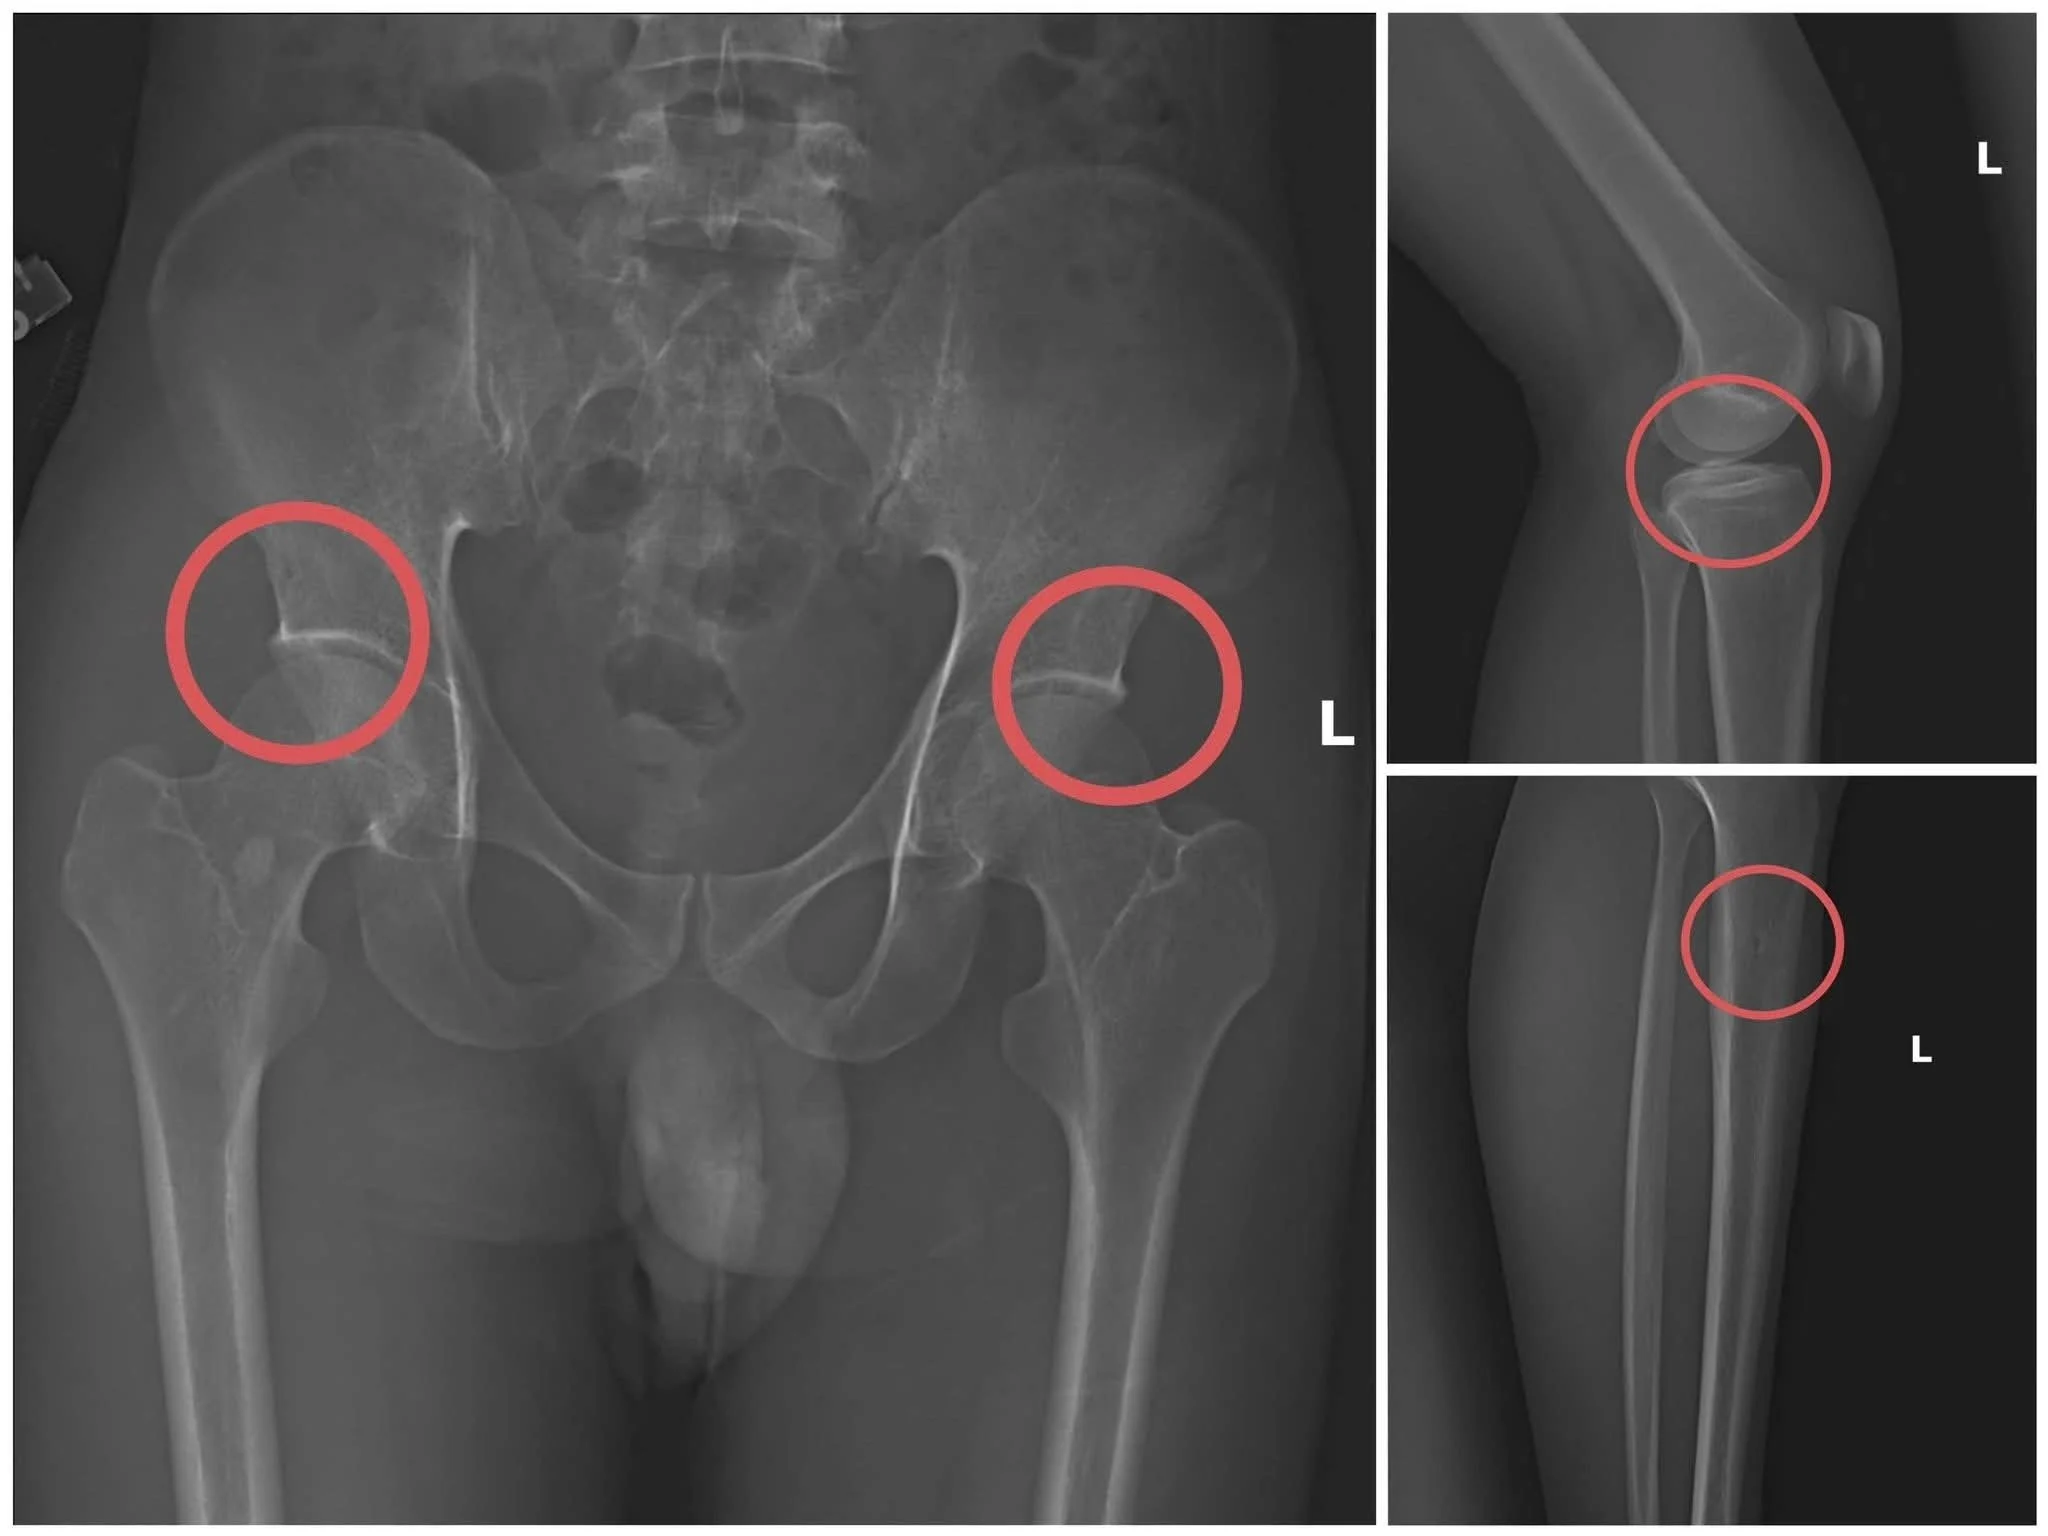

Điều khiến dư luận rúng động là Tạ Minh Châu đã trực tiếp thực hiện hành vi tiêm thuốc mê, sau đó sử dụng kim tiêm, búa và các công cụ khác để tác động lên xương người mua bảo hiểm, tạo ra các vết nứt, vỡ xương khớp tương tự như một tai nạn thật sự.

Hình ảnh một bản phim chụp X-Quang những tổn thương do đối tượng Châu tự tạo. Ảnh: Công an tỉnh Phú Thọ.

Thiếu tướng Nguyễn Minh Tuấn, Giám đốc Công an tỉnh, nhận định thủ đoạn này không chỉ tàn nhẫn, vô nhân tính và coi thường tính mạng người tham gia, mà còn được tính toán kỹ lưỡng nhằm gây thương tích đúng vị trí có mức chi trả cao, khiến các công ty bảo hiểm khó lòng phát hiện dấu hiệu gian dối.

Khu vực các đối tượng tiến hành can thiệp xương. Ảnh: Công an tỉnh Phú Thọ.